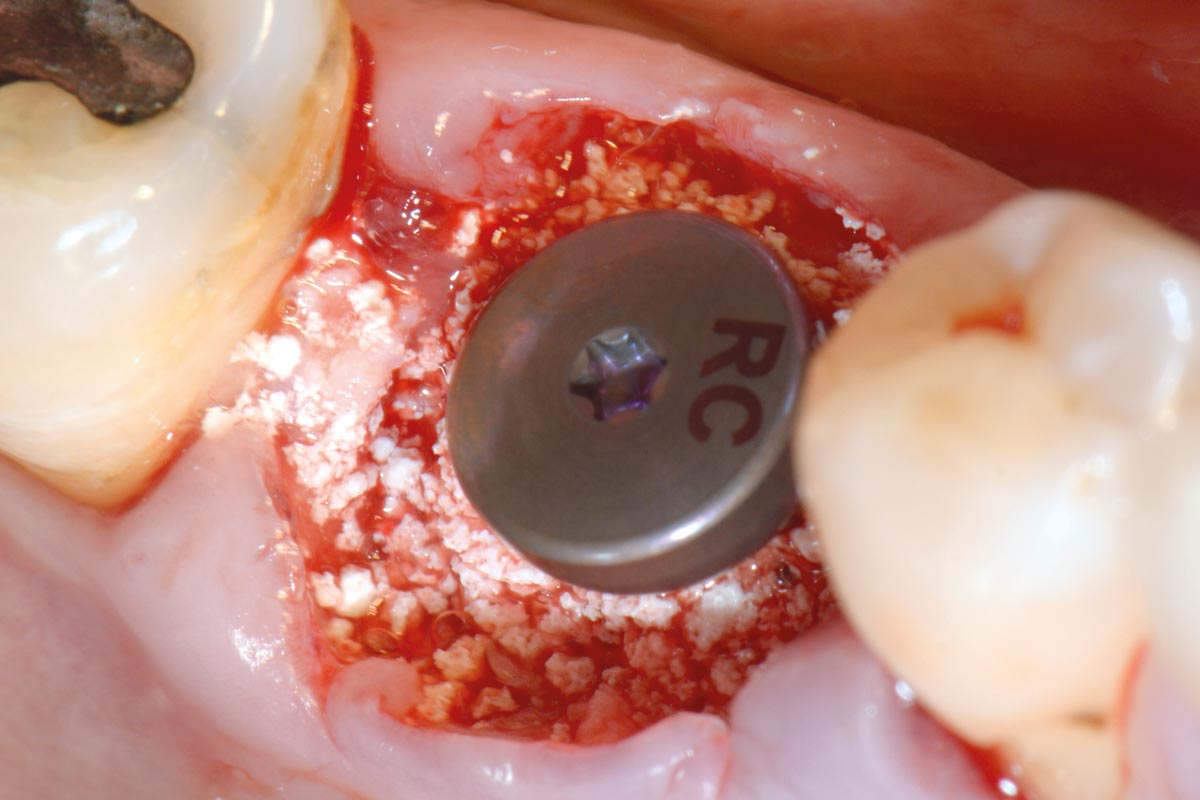

Covering of an immediately placed implant with permamem® - Prof. Z. Mazor

Immediately placed implant covered with permamem®. permamem® passively immobilized by sutures and intentionally left exposed to the oral cavity.